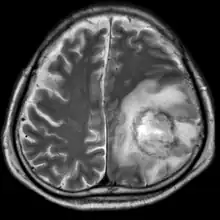

![]() | |

| T2-weighted MRI showing a necrotic brain absess as a result of GAE caused by an infection of Acanthamoeba, genotype T18 | |